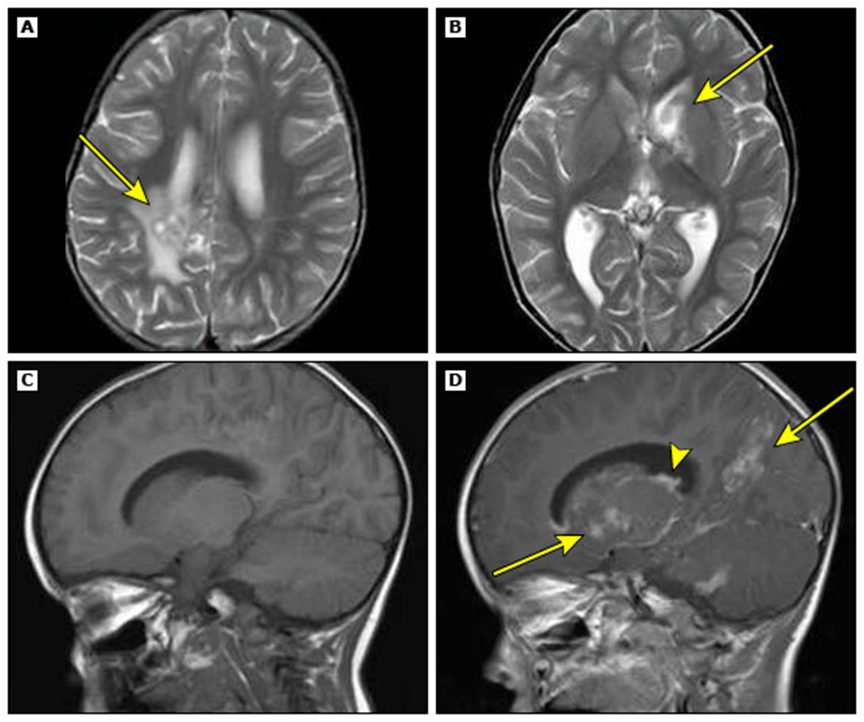

–მწვავე დისემინირებული ენცეფალომიელიტი – თეთრი ნივთიერების ღრმა და სუბკორტიკალური დაზიანებები, როგორც წესი, მრავლობითი და ორმხრივია, მაგრამ შეიძლება ასიმეტრიული იყოს (სურათი 2). ხშირია ტვინის ღეროს და ზურგის ტვინის ანომალიები. ნაცრისფერი ნივთიერების დაზიანებები შეიძლება შეინიშნოს თალამუსსა და ბაზალურ განგლიებში.

სურათი 2.

მწვავე დისემინირებული ენცეფალომიელიტის მქონე 7 წლის ბიჭის ტვინისა და ხერხემლის მაგნიტურ-რეზონანსული ტომოგრაფია.

(A) ტვინის აქსიალური T2-შეწონილი მაგნიტურ–რეზონანსული ტომოგრაფია აჩვენებს შედარებით სიმეტრიულ მაღალ სიგნალის ინტენსივობას ღრმა ნაცრისფერ ნივთიერებაში, მათ შორის ორმხრივ თალამუსში.

(B) ასევე მაღალია T2 სიგნალი ხიდის მარცხენა ასპექტში.

(C) კისრის ხერხემლის საგიტალური T2-შეწონილი მაგნიტურ–რეზონანსული ტომოგრაფია აჩვენებს გაფართოებას/შეშუპებას და მაღალ სიგნალის ინტენსივობას ზურგის ტვინში.

(D) შესაბამისი აქსიალური T2-შეწონილი მაგნიტურ–რეზონანსული ტომოგრაფია აჩვენებს, რომ მაღალი სიგნალი ძირითადად უკანაა.

(E და F) ერთი თვის შემდეგ, T2-შეწონილი ღერძული გამოსახულებები აჩვენებს ღრმა ნაცრისფერ ნივთიერებაში (E) და ხიდის ტვინში (F) არსებული მონაცემების გარჩევადობას.